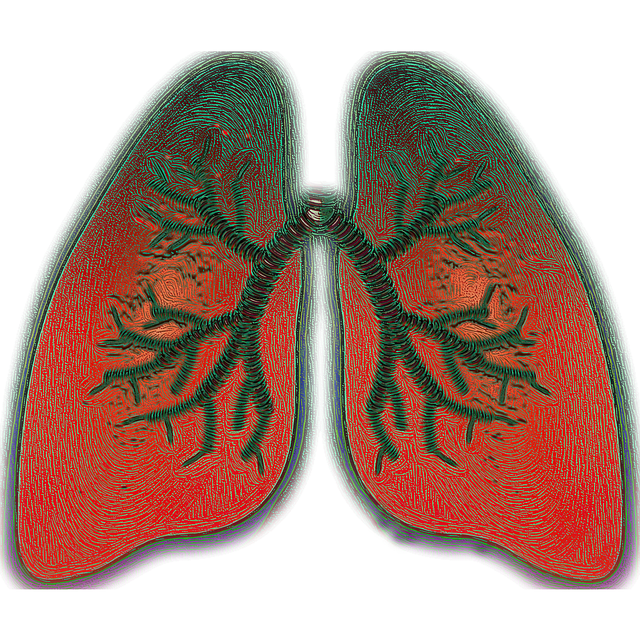

Inleiding

Ongeveer één op de tien Nederlanders heeft luchtwegklachten (ongeveer 1,6 miljoen mensen).

1 op de 50 Nederlanders heeft ernstige beperkingen door luchtwegklachten.

Ongeveer één op de tien Nederlanders heeft luchtwegklachten (ongeveer 1,6 miljoen mensen).

1 op de 50 Nederlanders heeft ernstige beperkingen door luchtwegklachten.

Dat zijn meer dan 300.000 mensen.

Twintig tot veertig procent van het ziekteverzuim in Nederland komt door luchtwegklachten!!!!!